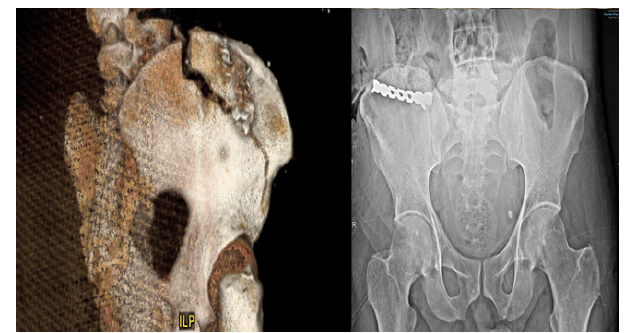

Regarding orthopedic surgical management, K-wires were initially used in 10 hands. Post operative X-Rays revealed 15 previously missed injuries (comprising 7 metacarpal fractures, 5 phalangeal fractures and 3 missed metallic foreign bodies). Of these 6 patients underwent secondary surgeries the following day, primarily for intramedullary pinning in case of metacarpal fractures (Figure 2), or standard pinning for phalangeal fractures while foreign bodies were removed at the bedside under local anesthesia.

Figure 2:Patient who presented with a severe injury and required revision surgery. A, B: Clinical status upon arrival. C, D, E: Post debridement and partial amputation. F: Post revision surgery the following day.

Figure 3:Preoperative and postoperative status of a patient who had a displaced iliac crest fracture.

Out of 45 included patients, only 3 had intact eyes and hands. The first one had the device in his pocket which only caused a wound to the abdominal wall with avulsion fracture of the anterior superior iliac spine. The second one was driving when the pager exploded on his lap which caused a deep wound to the right thigh associated with an iliac crest fracture requiring open reduction and internal fixation (Figure 3). The last individual sustained bilateral lower limbs injuries from projectile small fragments due to his relative proximity to the explosion.